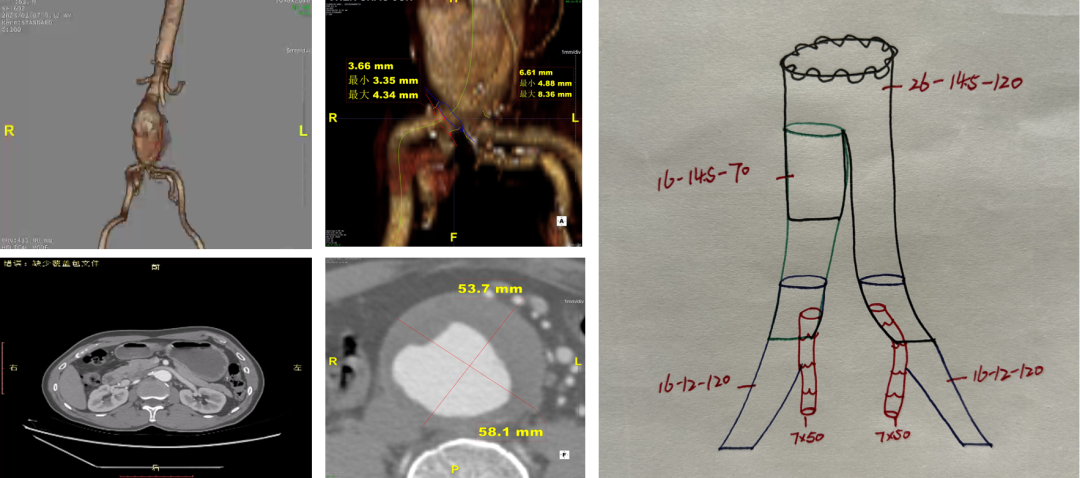

75岁男性 ,腹主动脉瘤合并右髂总动脉病变、左髂内动脉异位(游走左髂内动脉) ,采用商品化IBD支架 ,经术前造影、输送器改造、栓塞、支架释放及超选导入等操作 ,成功完成重建。

手术计划

1、栓塞肠系膜下动脉

2、最低肾动脉到腹主分叉处97mm,改装先健一代腹主支架--长分支齐平短分支

3、从IBD主体交叉超选左右髂内,完成重建

A:术前造影;B:XJZDF34120改装;C:肠下7mm,栓塞;D:主体支架释放

右侧IBD主体到位,超选、测量并导入右侧髂内支架;左侧IBD支架到位,超选、测量并导入左侧髂内支架